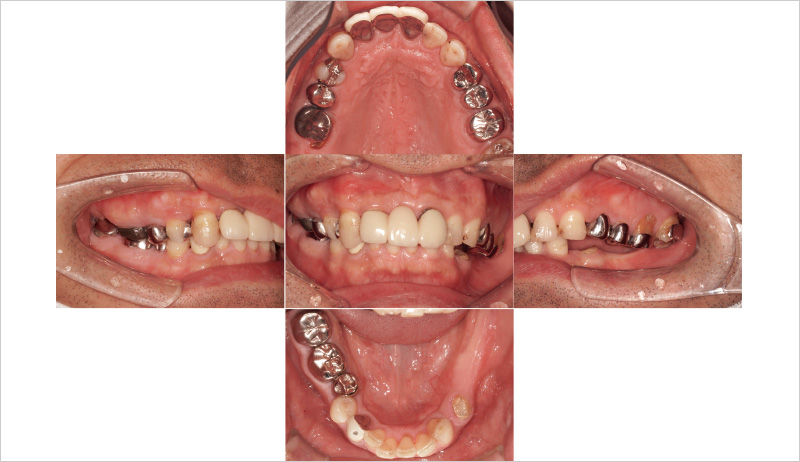

48歳男性、初診:2024年9月12日

主訴:左下の奥歯で噛めるようになりたい(図6, 7)。

₆、₇にインプラントを埋入し左側の咬合を得る治療計画を立案。φ4.5長さ9.5mmのSPIイニセルインプラント エレメントRCを埋入した(図8)。まずはここで初期固定を得られたのでヒーリングキャップにて封鎖した(図9)。今回は勤務医たちへの指導の意味もあり、ガイデッドサージェリーにて行った。そして4週目でクローズドトレーにてシリコン印象を行い補綴装置をセットした(図10,11)。CBCT撮影を行い骨レベルの状態を確認し、機能的審美的にも問題ないことがわかっている(図12, 13)。

![[写真] 初診時の口腔内写真](/academic/dentalmagazine/wp-content/uploads/sites/2/2025/09/194-8_photo06.jpg)

図6 初診時の口腔内写真 -

![[写真] 初診時のパノラマX線写真(2024年9月12日)](/academic/dentalmagazine/wp-content/uploads/sites/2/2025/09/194-8_photo07.jpg)

図7 初診時のパノラマX線写真(2024年9月12日) -